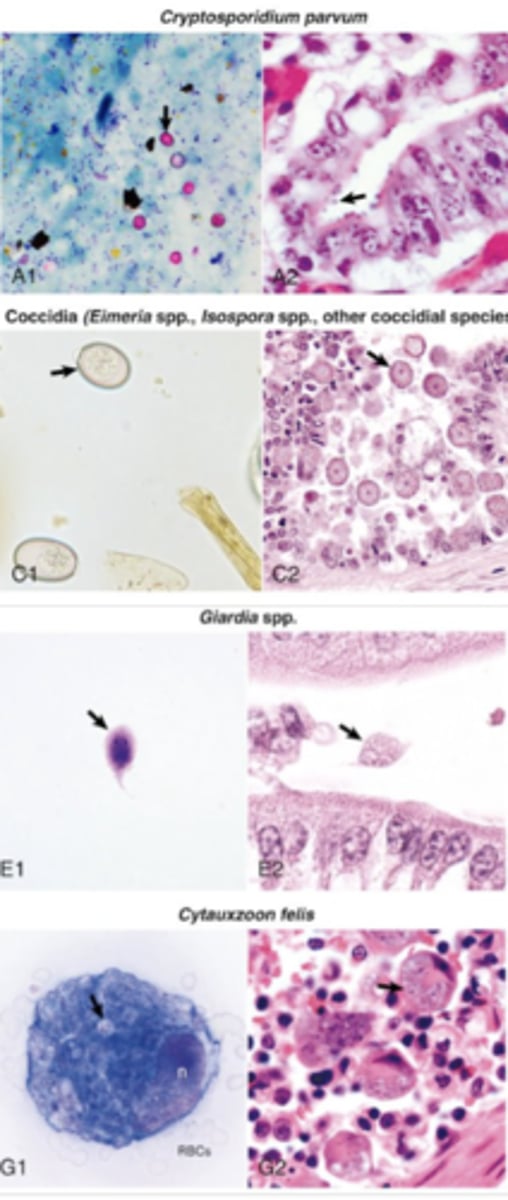

What broad group of pathogens does these images indicate ?

protozoa

What broad group of pathogens does these images indicate ?